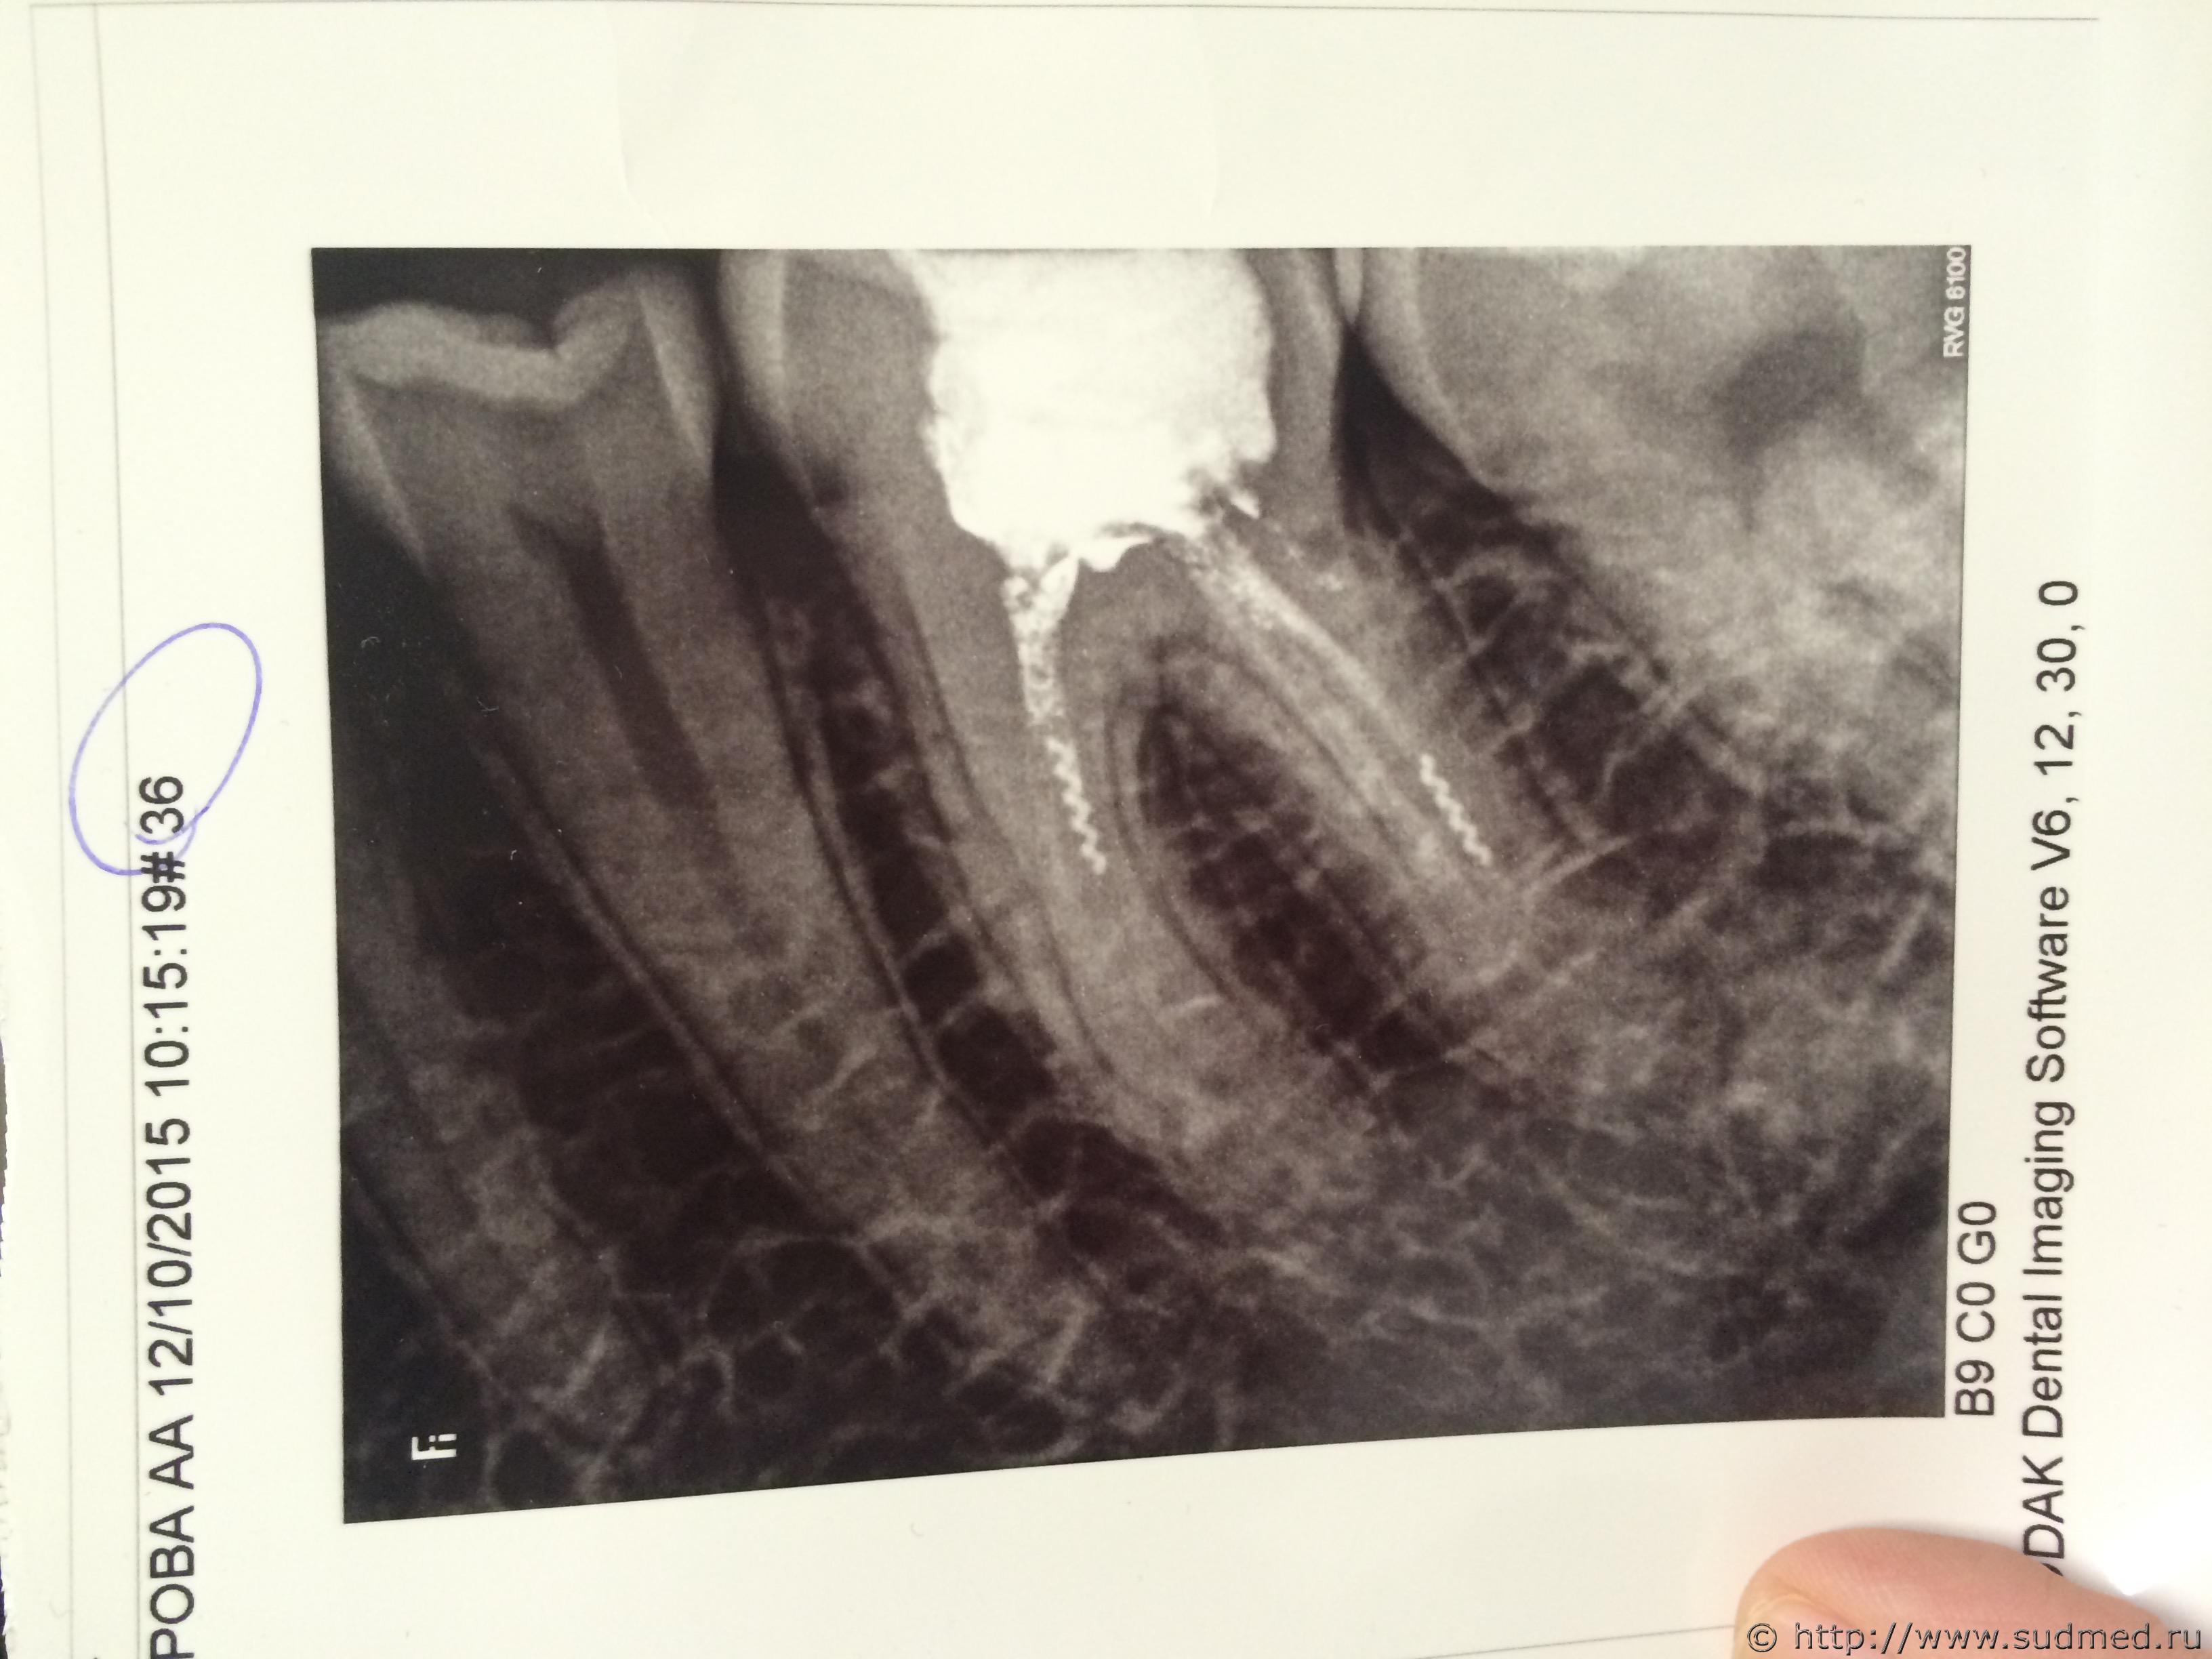

2 месяца назад обратилась в городскую стоматологическую поликлинику с острой болью в 36 зубе, мне поставили мышьяк (зуб болеть перестал через пару часов) и сказали приходить через неделю на пломбировку зуба. Так получилось, что мне пришлось открепиться от этой поликлинике по причине переезда и снимать мышьяк я пришла уже в стоматологическую поликлинику по новому месту жительства, там дежурный врач сказала, что видит что то в канале, и сказала придти через пару дней, сделать снимок и дальше поступать по ситуации. Далее я пришла , но попала к другому врачу, рассказала ему все, на снимок он не отправил, прочистил каналы иглой и сказал что все в порядке, через пару дней на пломбировку могу приходить (но зуб начал болеть снова, при том, что там стоял мышьяк). В следующий раз я попадаю к третьему врачу, которая наконец отправляет меня на !снимок! и оказывается, что в 2х каналах у меня инструменты. Далее долго пытались достать, обойти эти инородные предметы, но безуспешно. При расшифровке карты из поликлиники по прошлому месту жительства выяснилось что виноват врач из поликлиники по прошлому месту жительства, в 2009 году мне запломбировали эти каналы супер твёрдой пломбой, которую удалить не получится. Единственный вариант-удаление зуба, тк он болит. Зуб жевательный, следовательно после удаление ставить имплант и коронку, плюс моральный вред и вред здоровью.

Эскизы прикрепленных изображений

Судебная медицина - Прикрепленное изображение